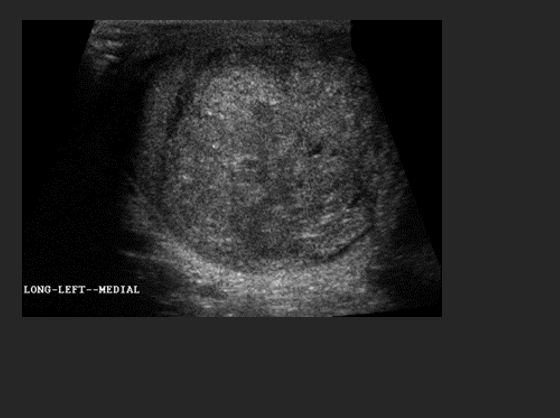

A 76 year old patient presents with a history of a palpable mass in the superior portion of the right scrotal sac. A nonvascular cystic mass is identified in the medial portion of the testis. This mass is most suspicious for what abnormality?

The contralateral testis in this patient will most likely demonstrate a

D. Tubular ectasia of the rete testis

– D. Tubular ectasia of the rete testis